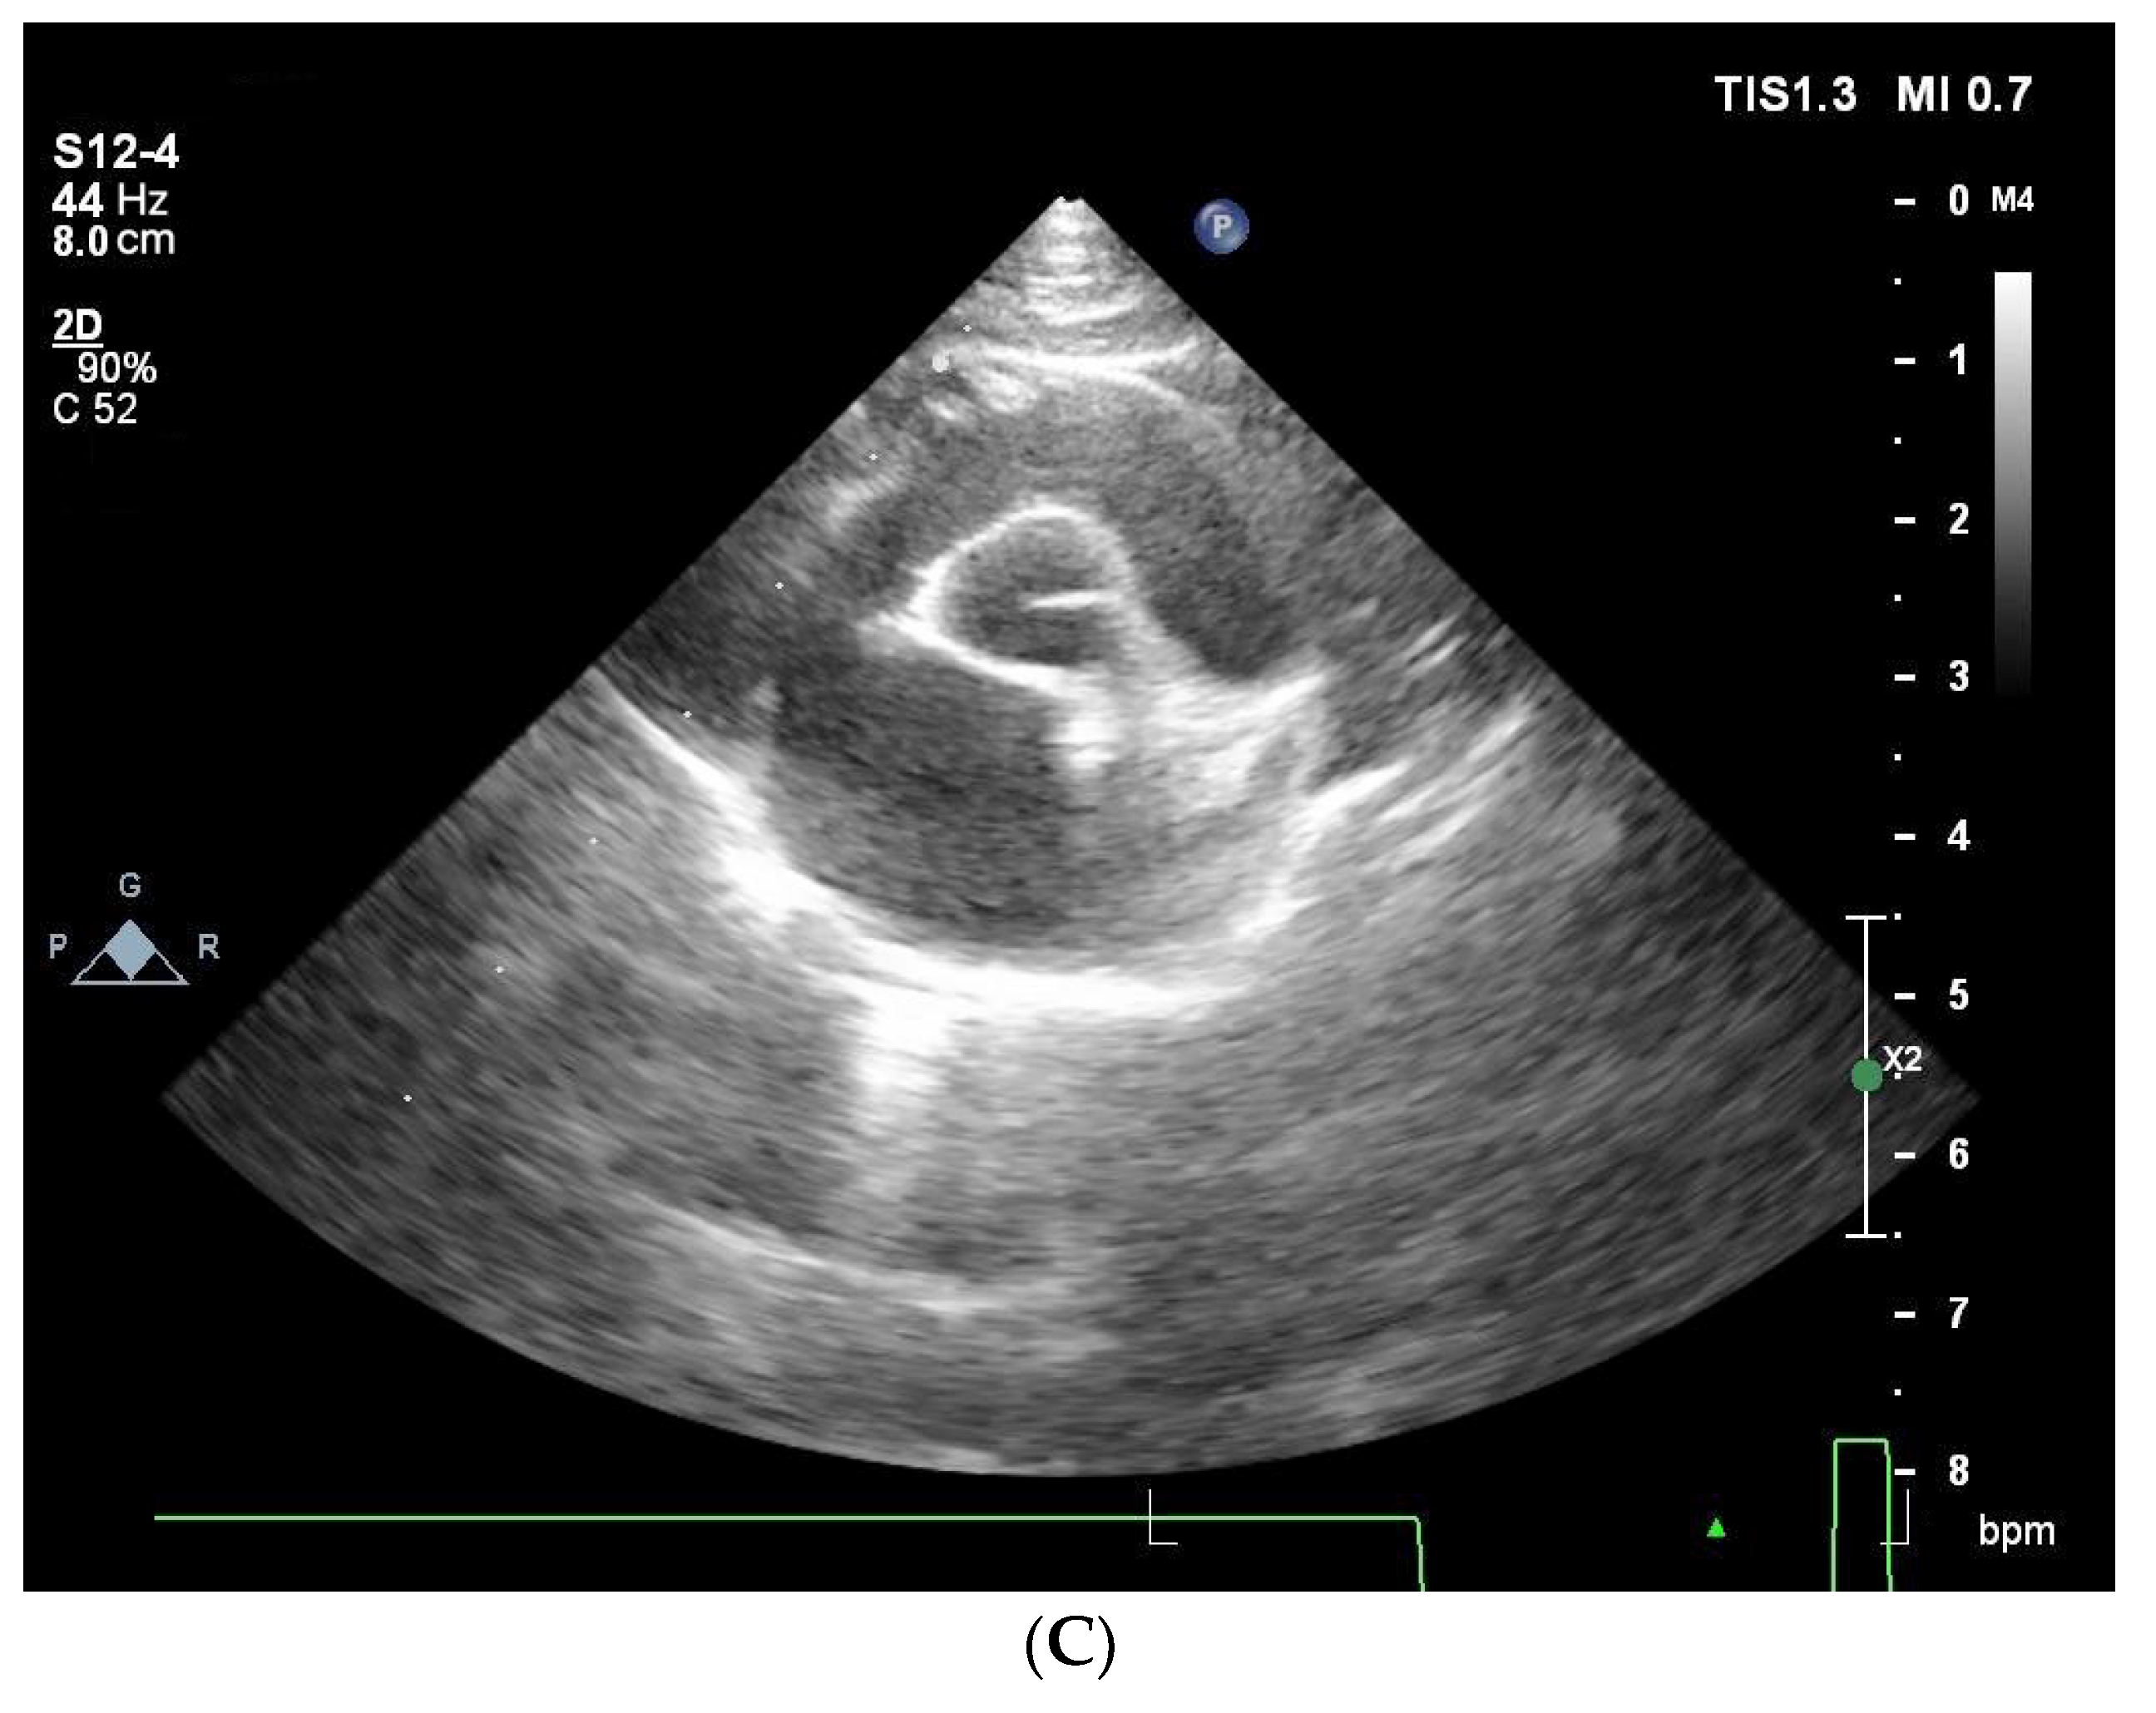

Anterior systolic mitral motion was identified in nine cats with severe to moderate HCM (Figure 1).

Figure 1. Echocardiographic images (cat, 10 years old, 7.6 kg, Domestic Shorthair), diagnosis: obstructive form of HCM (stage B2), demonstrating anterior systolic mitral motion. (A) transmitral flow, IVRT. (B) left ventricle in M-mode. (C) aorta in relation to the left atrium, dilatation of the left atrium.